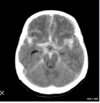

What type of herniation is depicted? Uncal Central (transtentorial) Cingulate (Subfalcine) Transcalvarial Upward cerebellar (transtentorial) Downward cerebellar (Tonsillar)

What type of herniation is depicted? Uncal Central (transtentorial) **Cingulate (Subfalcine)** Transcalvarial Upward cerebellar (transtentorial) Downward cerebellar (Tonsillar)